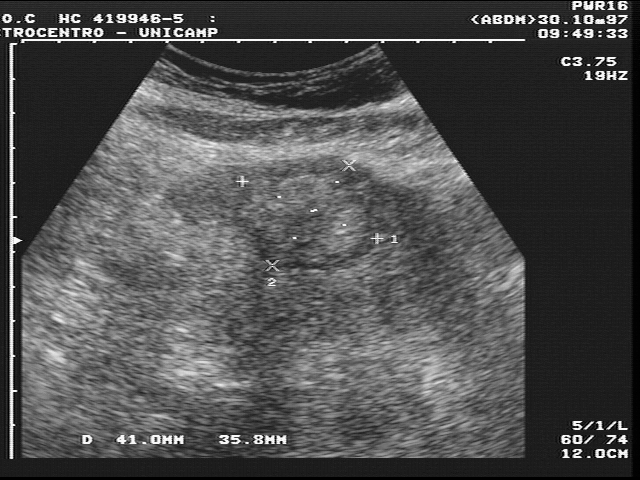

A ultrassonografia, também chamada ecografia, geralmente é o primeiro exame solicitado. Ela é indolor, não usa radiação, tem baixo custo e é amplamente disponível. Pelo ultrassom é possível detectar aumento ou diminuição do fígado, aspecto compatível com infiltração gordurosa, alterações sugestivas de hepatite crônica, dilatação das vias biliares, presença de cálculos, tumores em formação, nódulos benignos como hemangiomas, acúmulo de líquido no abdome (ascite) e alterações nos vasos que sugerem hipertensão portal, como dilatação da veia porta e do baço. O ultrassom também é muito útil como ferramenta de triagem para câncer de fígado em pessoas com cirrose, sendo recomendado em intervalos regulares. Apesar disso, tem limitações: sua precisão depende muito do operador e de condições técnicas, especialmente em pacientes com obesidade ou excesso de gases intestinais.